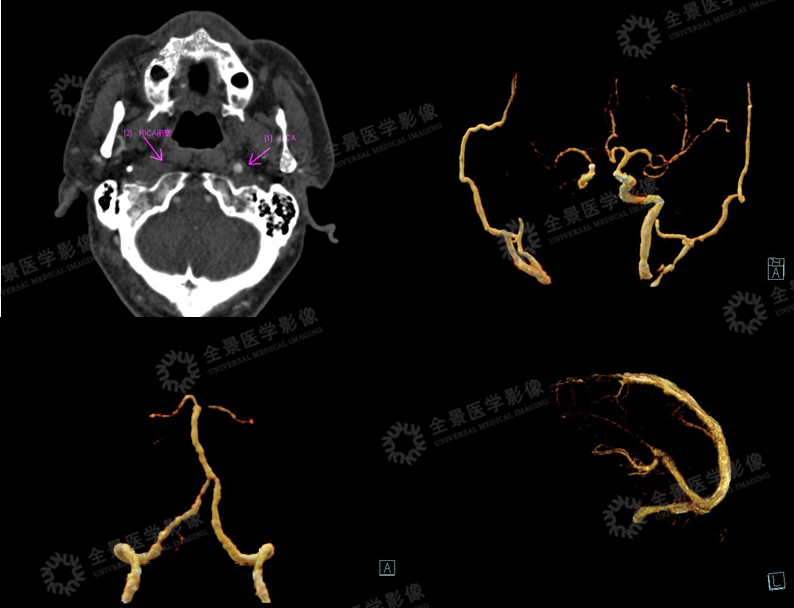

利用灌注的原始数据评估脑血管情况

CTA未见明显异常。

一站式灌注血管成像示:脑动脉未见明显异常。

脑静脉成像可见右侧乙状窦、岩窦较左侧管径增宽,临近右枕叶脉络从静脉血管丰富。

临床诊断为:右枕叶颜面血管瘤综合征(Sturge-Weber综合征)